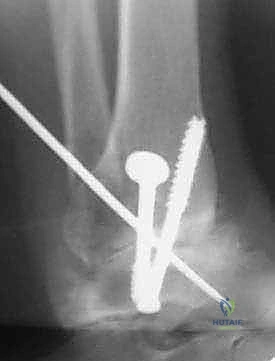

- التثبيت الصلب (Rigid Fixation): يتم تثبيت العظام في وضعيتها الجديدة باستخدام مسامير طبية كبيرة مجوفة (Cannulated Screws) مصنوعة من التيتانيوم. يتم إدخال هذه المسامير عبر العظام بتقنية متقاطعة لضمان أقصى درجات الثبات والضغط بين السطحين العظميين.

- الترقيع العظمي (Bone Grafting): لتعزيز الالتئام، يتم استخدام الجزء الذي تم قطعه من عظم الشظية وتثبيته كجسر داعم عبر المفصل المدمج، أو يتم طحن أجزاء من العظام الزائدة واستخدامها كطعم عظمي ذاتي لملء أي فراغات.